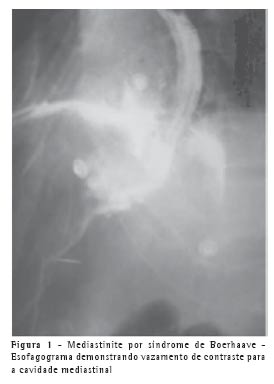

Como causa de mediastinite aguda, a esternotomia mediana foi a mais freqüente, responsável por 38,1% dos casos, seguida de perto pela ruptura esofágica com 33,3% dos casos. Como etiologia da ruptura esofágica foram encontradas: ruptura pós-endoscopia digestiva alta/dilatação, com 3 casos; ruptura espontânea - síndrome de Boerhaave - 2 casos; ruptura traumática e por corpo estranho, cada uma com 1 caso. As infecções da cabeça e pescoço corresponderam a 3 casos (14,3%), sendo 2 de abscessos cervicais profundos e 1 caso de angina de Ludwig (Figuras 1, 2 e 3). A mediastinoscopia, a piopericardite e o empiema pleural contribuíram cada um com 1 caso de mediastinite aguda (4,8%).

A partir da suspeita clínica, a radiografia de tórax deve ser solicitada. Esta já pode evidenciar sinais de mediastinite ou complicações da mesma, como enfisema de mediastino e derrame pleural. A tomografia de tórax com janela para mediastino complementa a radiografia, mostrando abscessos mediastinais, enfisemas, comprometimento esternal, etc.; com mais detalhes.(1,6) Nos casos suspeitos de síndrome de Boerhaave, o esofagograma contrastado é de fundamental importância, visto que sela o diagnóstico ao mostrar o extravasamento do contraste para o mediastino.